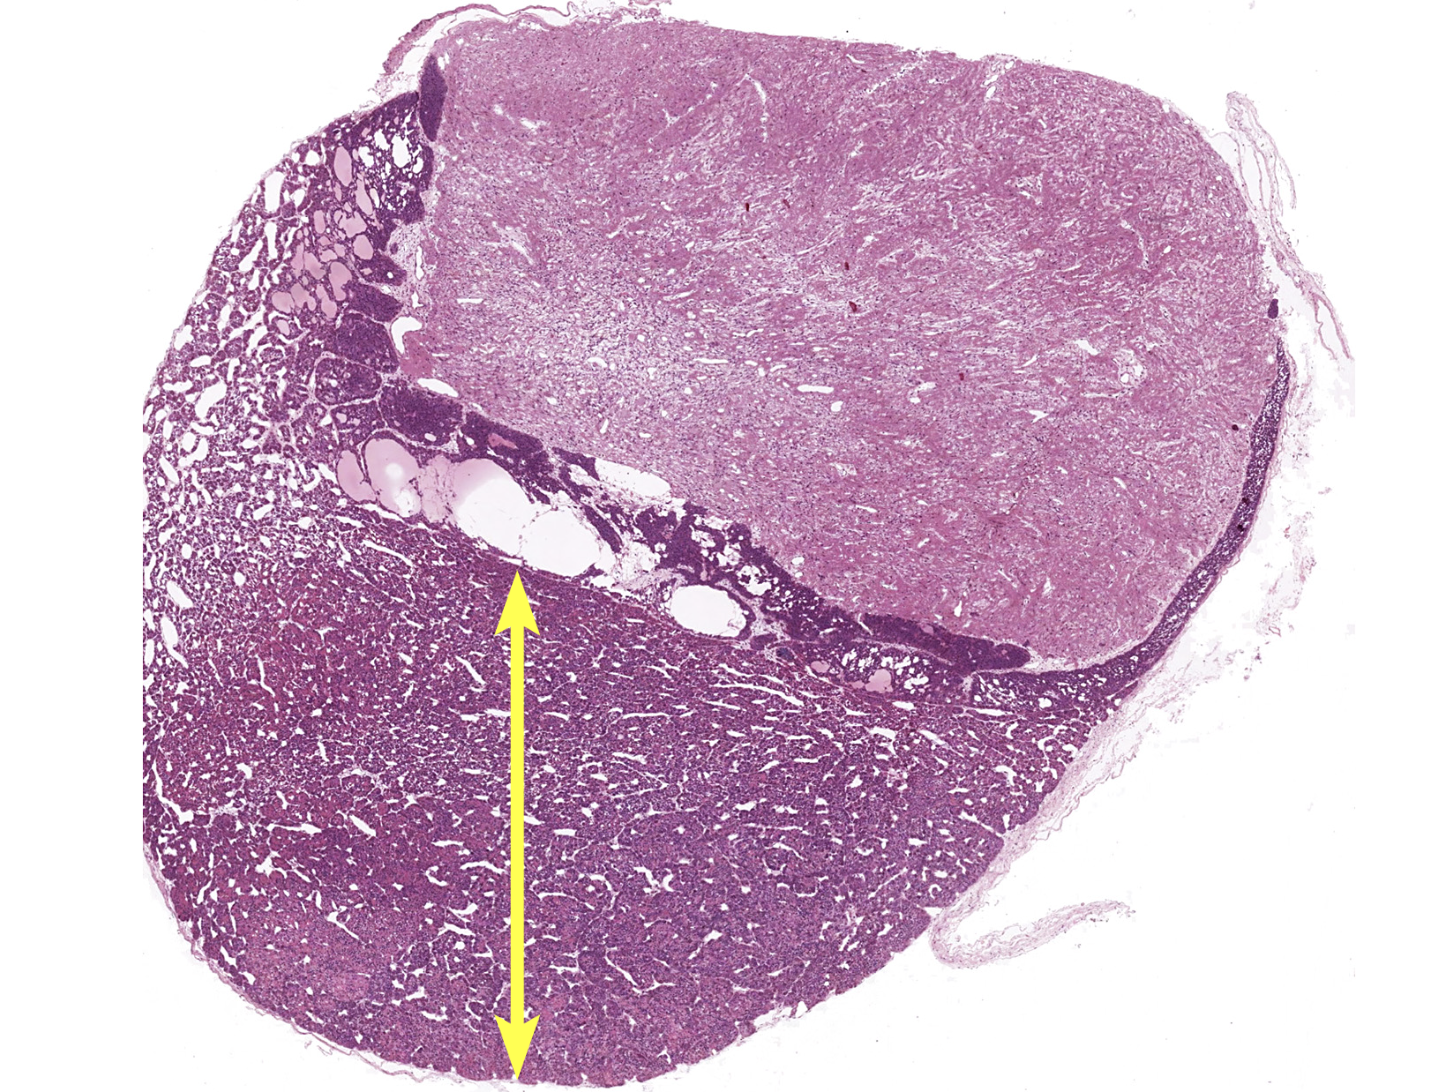

adrenal gland

adrenal cortex

zona glomerulosa

zona fasciculata

zona reticularis

adrenal medulla